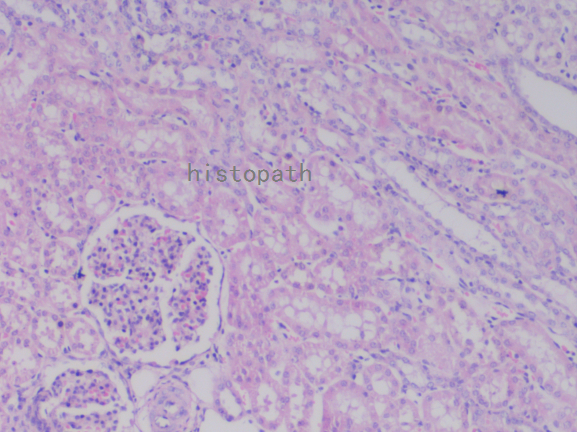

苏木精--伊红染色法(hematoxylin-eosin staining),简称HE染色法,石蜡切片技术里常用的染色法之一。苏木精染液为碱性,主要使细胞核内的染色质与胞质内的核酸着紫蓝色;伊红为酸性染料,主要使细胞质和细胞外基质中的成分着红色。HE染色法使组织学、胚胎学、病理学教学与科研中最基本、使用最广泛的技术方法。

染色结果:

细胞核呈蓝色,细胞质、肌肉、结缔组织、红细胞、嗜曙红颗粒呈不同程度的粉红色。钙盐、软骨基质和各种微生物也可染成蓝色或紫蓝色。核仁呈红色。着色情况不仅与组织或细胞的种类有关,也随其生活周期及病理变化而改变。质量优良的HE染色切片样本,细胞核与细胞质蓝红对比明显,胞核鲜明,核膜及核染色质颗粒均清晰可见。